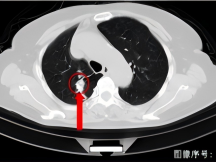

术后9+年,患者再次到我院复查胸部CT,发现右上肺上方(尖段)新增结节,诊断为转移瘤,征得患者及家属同意后,再次为患者实施右上肺尖段新增结节碘125粒子植入技术,进一步为患者稳定病灶。

术后9+年复查

右上肺尖段新增结节碘125粒子植入